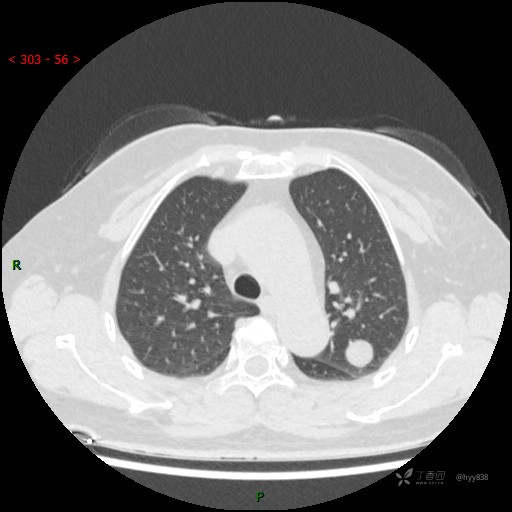

静脉期

各期CT值:28hu、58hu、69hu